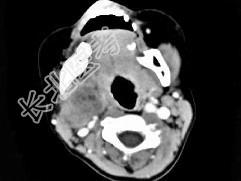

- 单项选择题女,4岁, 右侧颈部可扪及一包块约两个月,无热无痛, CT如图所示,最可能的诊断为  (    )